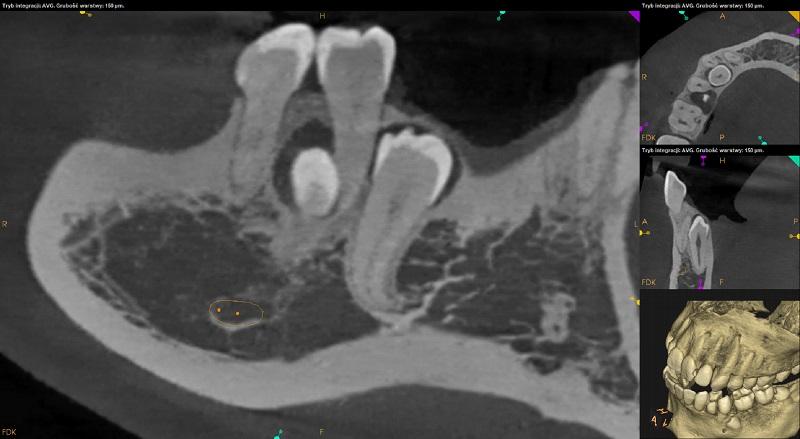

Pomiędzy korzeniami zębów 24 i 25 widoczny zatrzymany ząb nadliczbowy. Położony pionowo. Wierzchołek korzenia zagięty, wpukla się do swiatła zatoki szczękowej. Widoczna dyskretna resorpcja korzenia podniebiennego zęba 24 i policzkowego zęba 25.